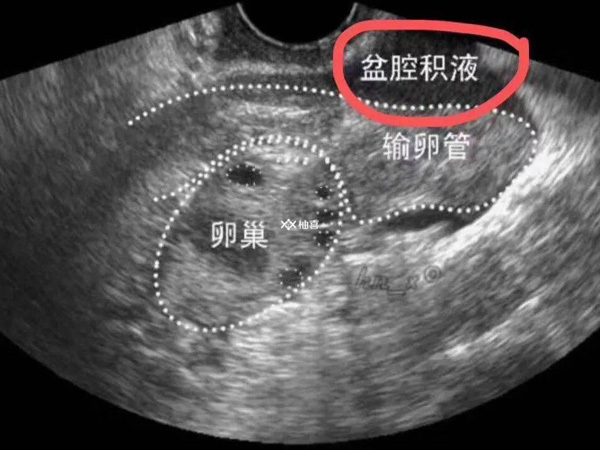

有盆腔积液能否移植取决于病情,如果只有少量积液那么就可以移植,因为大部分积液会自动被吸收,症状是下腹疼痛、腰酸不适等。一般来说,当盆腔积液小于5mm时,属于正常情况。如果大于5mm,属于脓性和血性渗液,且数量较多,则不能移植。如果是病理性盆腔积液,那么在移植前需要先进行治疗。